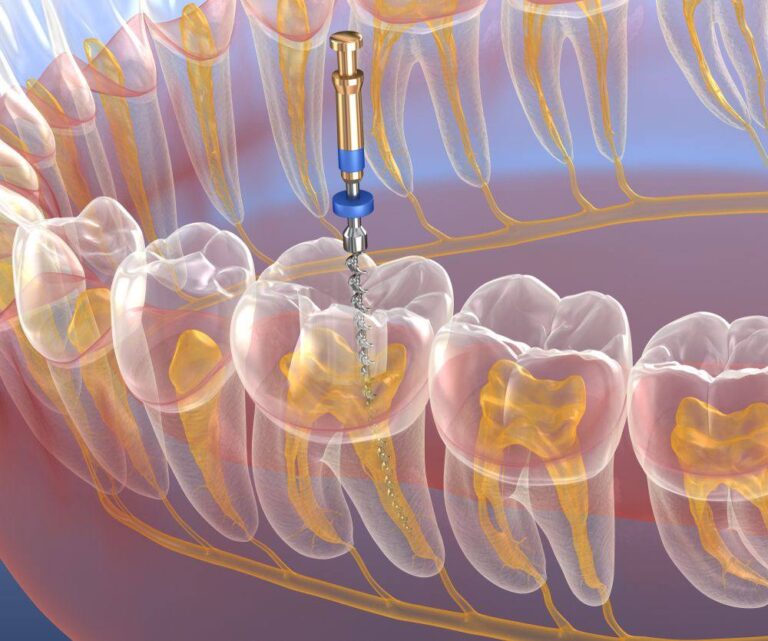

درمان ریشه یکی از حساسترین و دقیقترین درمانهای دندانپزشکی است و کوچکترین خطا در طول کار میتوان…

درمان ریشه مجدد یا اندودانتیک مجدد (Re-Endo)، یکی از درمانهای تخصصی دندانپزشکی است که زمانی انجام …